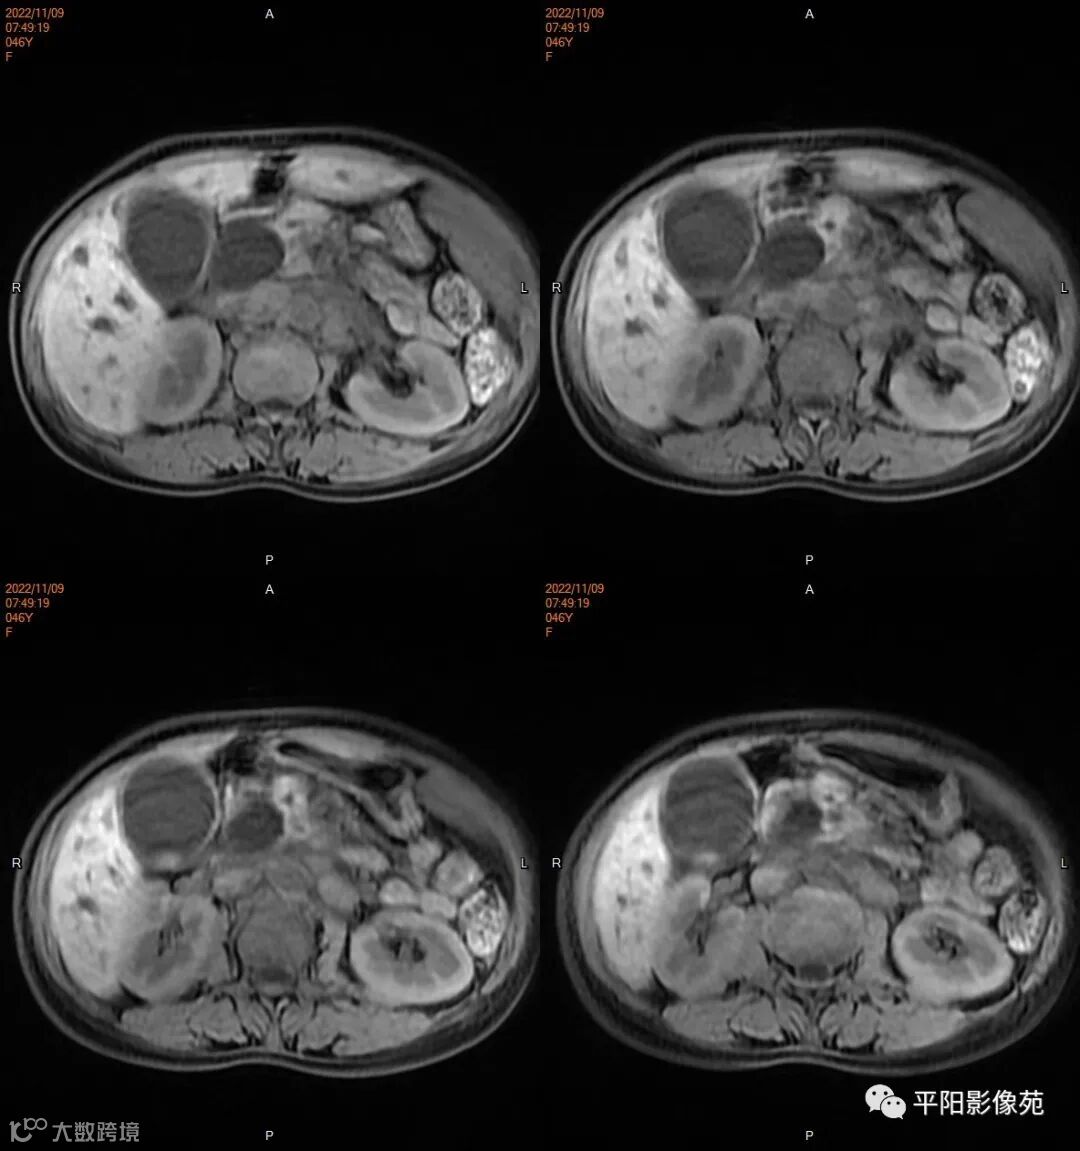

影像学检查

MR

影像表现: